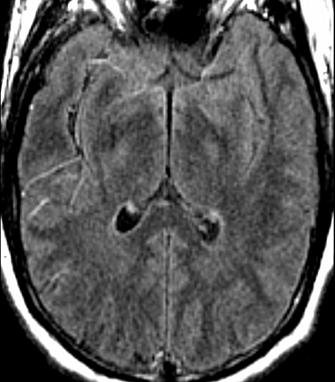

IRM cérébrale, séquence FLAIR : aspect normal à H2